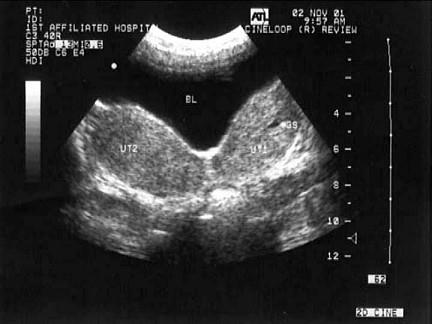

问题 女性,28岁,停经42天,血HCG258μg/ml。结合超声图像,最可能的诊断为?(?)

选项 A.畸胎瘤 B.卵巢癌 C.双子宫并早期妊娠 D.子宫浆膜下肌瘤 E.双子宫并宫腔积液

答案 C